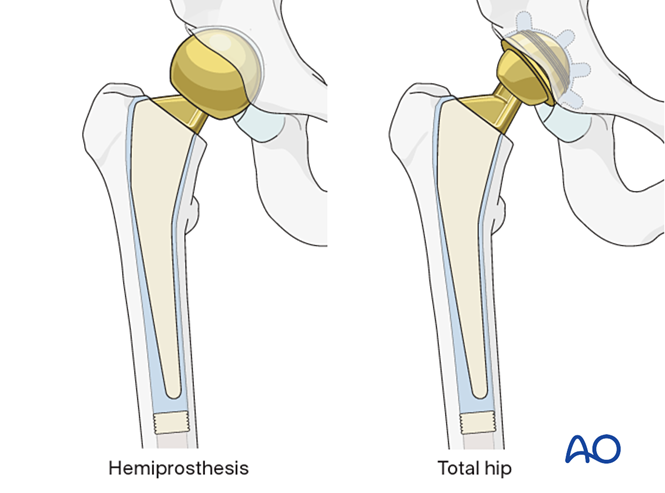

半髋置换 vs 全髋置换对于股骨颈骨折,术者需在多种关节置换术式中选择:首先决定行骨折固定还是关节置换。若选择关节置换,则需确定类型:半髋置换(置换股骨头及股骨颈)或全髋置换(同时置换股骨头、股骨颈及髋臼表面)。半髋置换●手术较简单,对低活动度老年患者效果普遍满意。●费用更低,脱位风险低于全髋置换,但可能导致髋臼疼痛及磨损,需后期翻修。

全髋置换●文献报道全髋置换治疗股骨颈骨折的效果持续改善,因此对移位股骨颈骨折(尤其高活动度老年患者)愈发受青睐。●术前存在骨关节炎者亦适用。仅建议由经验丰富的术者实施。

全髋置换主要适应症●术前存在髋关节骨关节炎或炎性关节炎的股骨颈骨折患者。●模块化半髋假体转为全髋假体